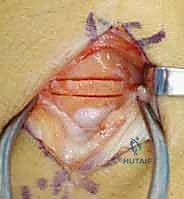

1. يقوم الدكتور هطيف بفتح شق جراحي دقيق في الرسغ (عادة من الناحية الظهرية أو البطنية حسب مصدر الطعم).

2. يتم تحديد قطعة صغيرة من العظم السليم من منطقة قريبة (غالباً من عظمة الكعبرة السفلية - Distal Radius).

3. الجزء الحاسم: لا يتم أخذ العظم فحسب، بل يتم استئصاله مع الشريان والوريد المتصلين به (Pedicled graft). هذا يعني أن قطعة العظم المنقولة لا تزال حية وتنبض بالدم.

4. يتم تنظيف العظم الهلالي الميت وتفريغه من الأنسجة الميتة (Core Decompression).

5. يُزرع الطعم العظمي الحي (الوعائي) داخل التجويف الذي تم إنشاؤه في العظم الهلالي.

6. تعمل الأوعية الدموية المنقولة كـ "شريان حياة" جديد، حيث تبدأ في تغذية العظم الهلالي، مما يحفز الخلايا العظمية (Osteoblasts) على بناء نسيج عظمي جديد وقوي.